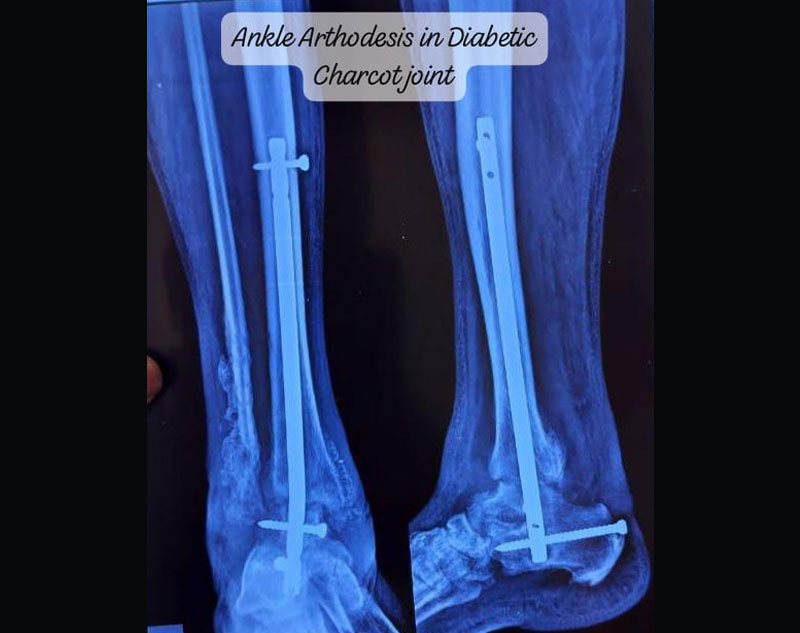

Foot and ankle surgeries are medical procedures performed to treat injuries, deformities, or conditions affecting the bones, joints, ligaments, tendons, or soft tissues of the foot and ankle. These surgeries can address acute injuries, chronic conditions, or congenital abnormalities and are performed by orthopedic surgeons specializing in foot and ankle issues.